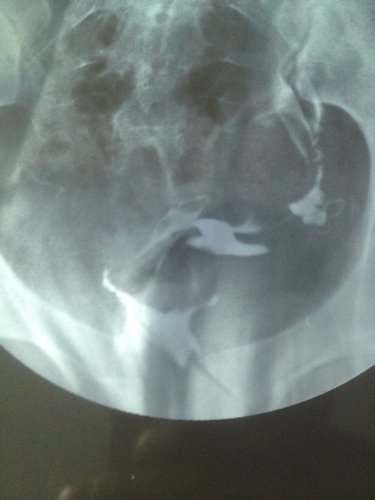

帮我看看这个X光照影,输卵管通不通?粘连吗? 点击展开 匿名用户 2014-07-22 10:32 为您推荐: 其他回答 你好,这个不一定的,平时的时候亲最好让大夫详细的检查一下比较放心的哦,平时多注意休息 斑驳的流年88 2014-07-22 10:35 相关问题 郑州怎么查输卵管通不通?输卵管不通粘连 我吃了活血化瘀的中药左侧附件隐隐作痛是什么原因呢(曾宫外孕切除了右侧输卵管)(现在左侧伞端粘连不通 子宫右倾,宫劲宫腔重度粘连,右侧输卵管不通??